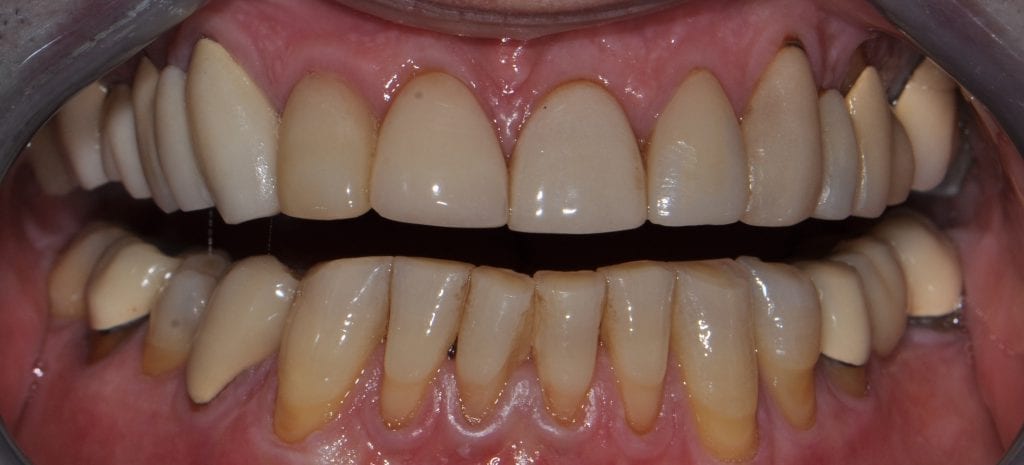

Pre-existing restorations that warranted replacement with an increase in vertical dimension.

Pre-existing restorations that warranted replacement with an increase in vertical dimension. The upper and lower arch were captured with the medit I500 and articulated together with enough clearance to accommodate new restorations and to restore the patient to an ideal tooth position.